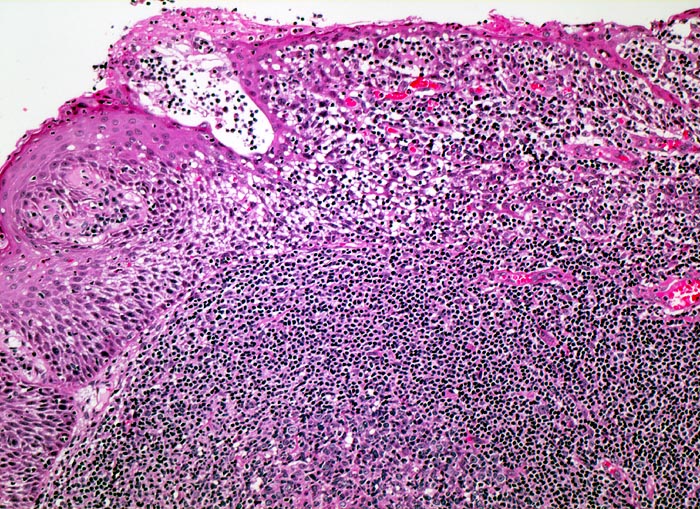

Tonsille mit Sekundärfollikel

Ein sekundärer Lymphfollikel mit angeschnittenem Keimzentrum wird bedeckt von Plattenepithel der Mundschleimhaut. Zahlreiche Lymphozyten infiltrieren das darüberliegende Epithel, was in der Tonsille ein Normalbefund darstellt.

Histologie

100